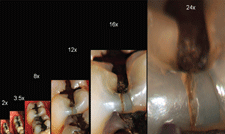

Figures 2c-g: At 8X magnification the Bioclear Diastema Closure Matrix can be

truly appreciated as the gingival apron is inserted gently and deeply into the sulcus.

In Fig. 2f, we can see that too much distal pressure is being placed on the matrix and

it is beginning to invert. 2g demonstrates the ideal adaptation pressure and the first

small layer of flowable composite has been placed and light cured.